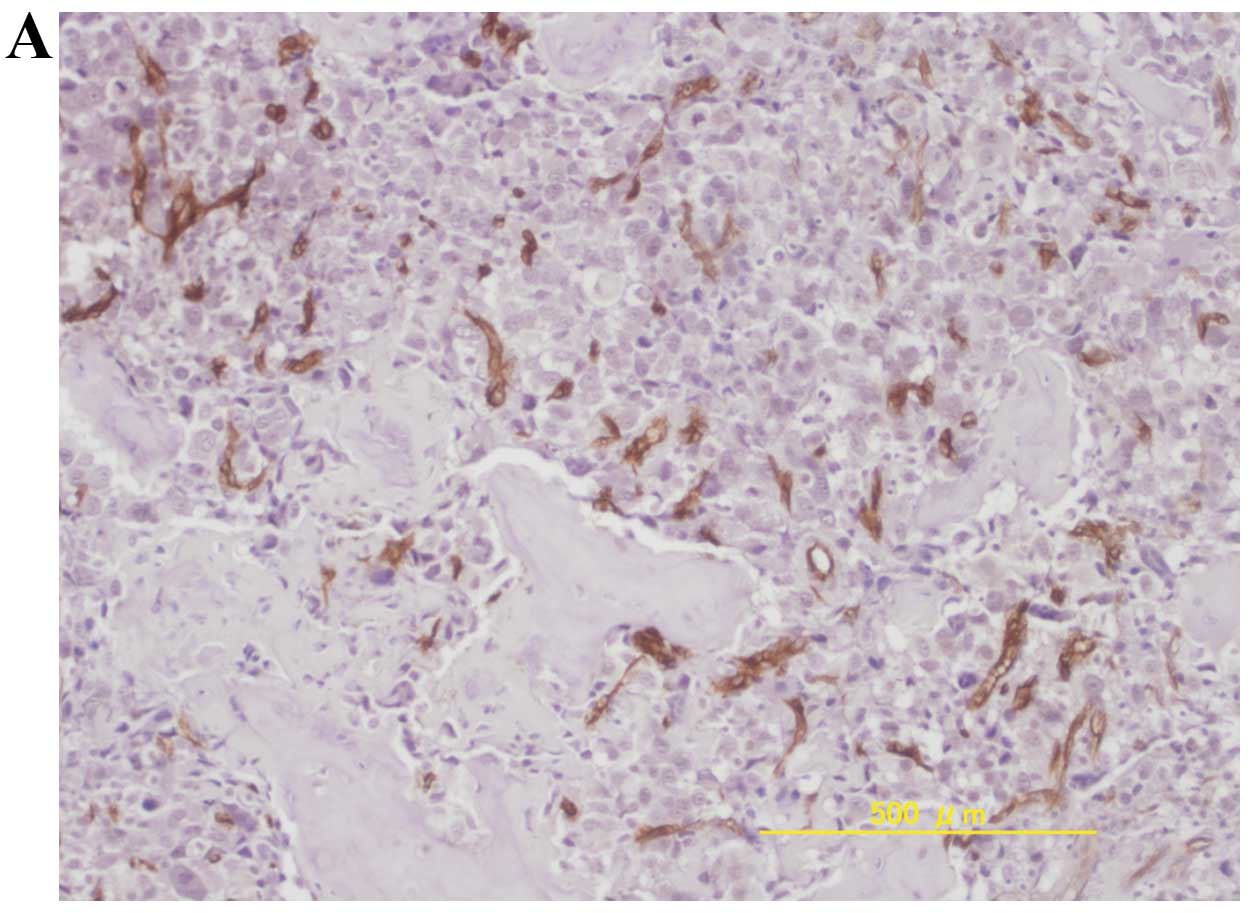

Diversity of angiogenesis among malignant bone tumors

Several studies have demonstrated that angiogenesis assessed by microvessel density (MVD) correlates with patient prognosis in various types of cancer, whereas data regarding the relevance of angiogenesis and prognosis in malignant bone tumors are scarce and controversial. The aim of this study was to examine MVD in representative malignant bone tumors, such as osteosarcoma, chondrosarcoma and Ewing's sarcoma, in order to clarify the role of angiogenesis in prognosis. A total of 69 patients with malignant bone tumors, including 44 osteosarcomas, 20 chondrosarcomas and 5 Ewing's sarcomas, were reviewed retrospectively and treated at our hospital between 1980 and 2007. Biopsy or pre-chemotherapy surgical specimens were immunohistochemically stained with anti-CD34 antibody. The MVD values of osteosarcomas and Ewing's sarcomas were significantly higher compared to chondrosarcoma. In osteosarcomas with high MVD, American Joint Committee on Cancer stage IIA, good histological response to chemotherapy was significantly correlated with better disease-free survival, while MVD was closely associated with age and chemotherapy response. In chondrosarcomas, the surgical margin (marginal and intralesional), MVD (high), tumor size (≥8) and histological grade (grades 2 and 3) significantly correlated with a shorter disease-free survival, while MVD was closely associated with age and histological grade. These findings showed that osteosarcomas and Ewing's sarcomas were hypervascular, compared to chondrosarcomas. In osteosarcomas, hypervascularity induced good chemotherapy response, leading to better prognosis, while in chondrosarcomas, high MVD was associated with histological grade and predicted poor prognosis.